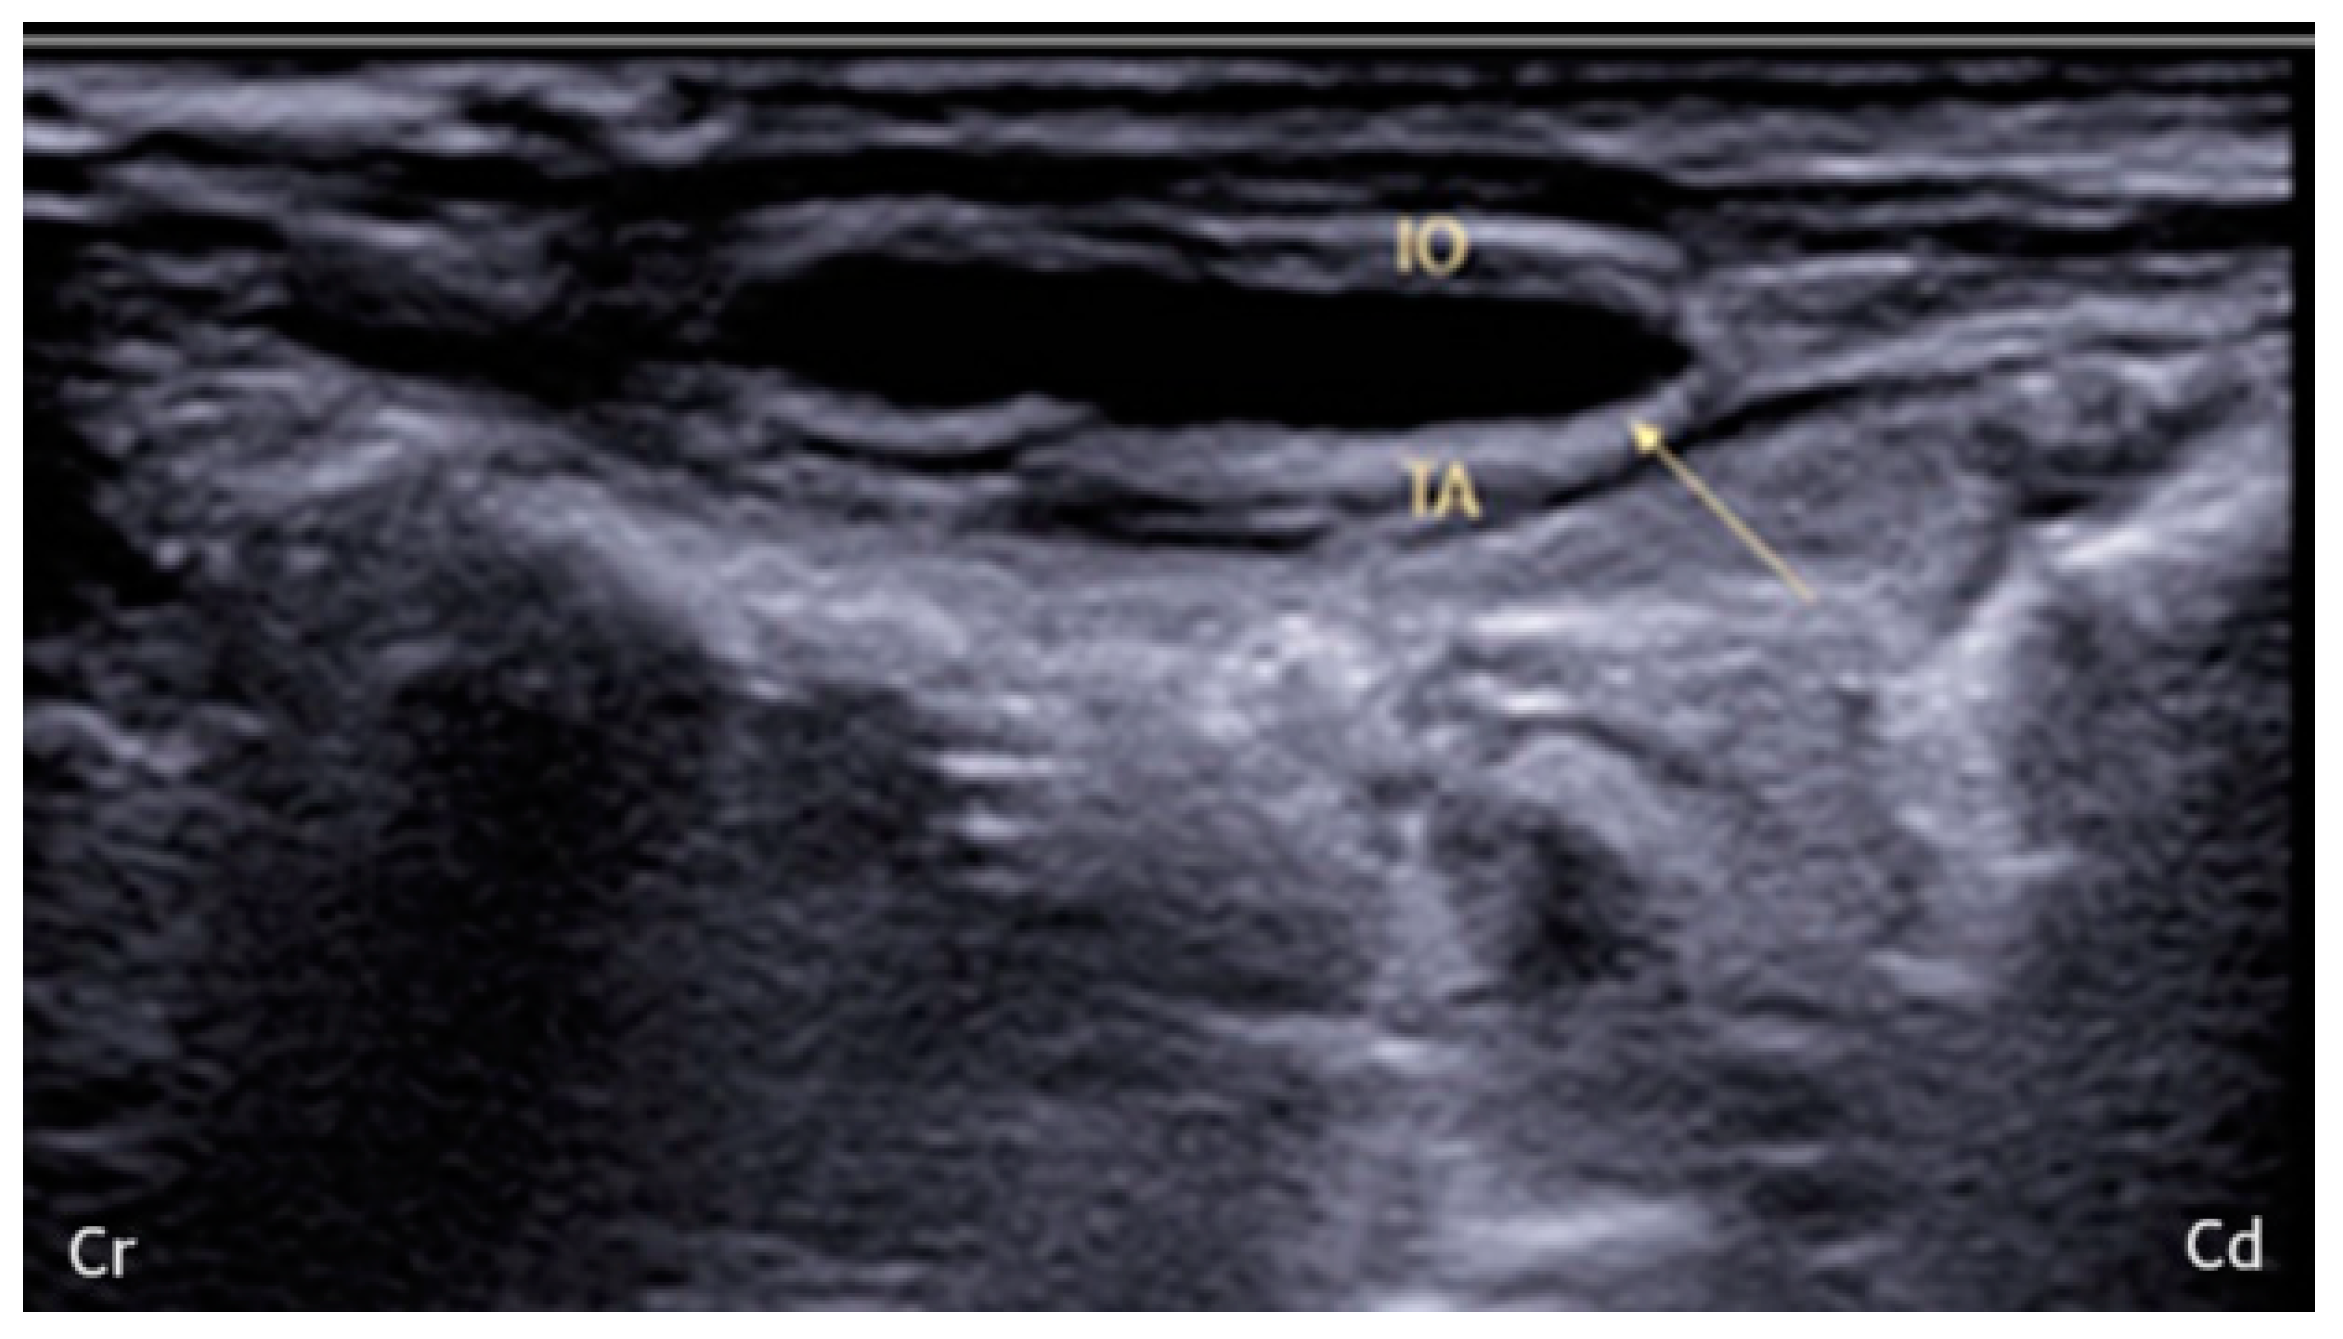

2.1. US-Guided TAP Injection

3.1. US-Guided TAP Injection